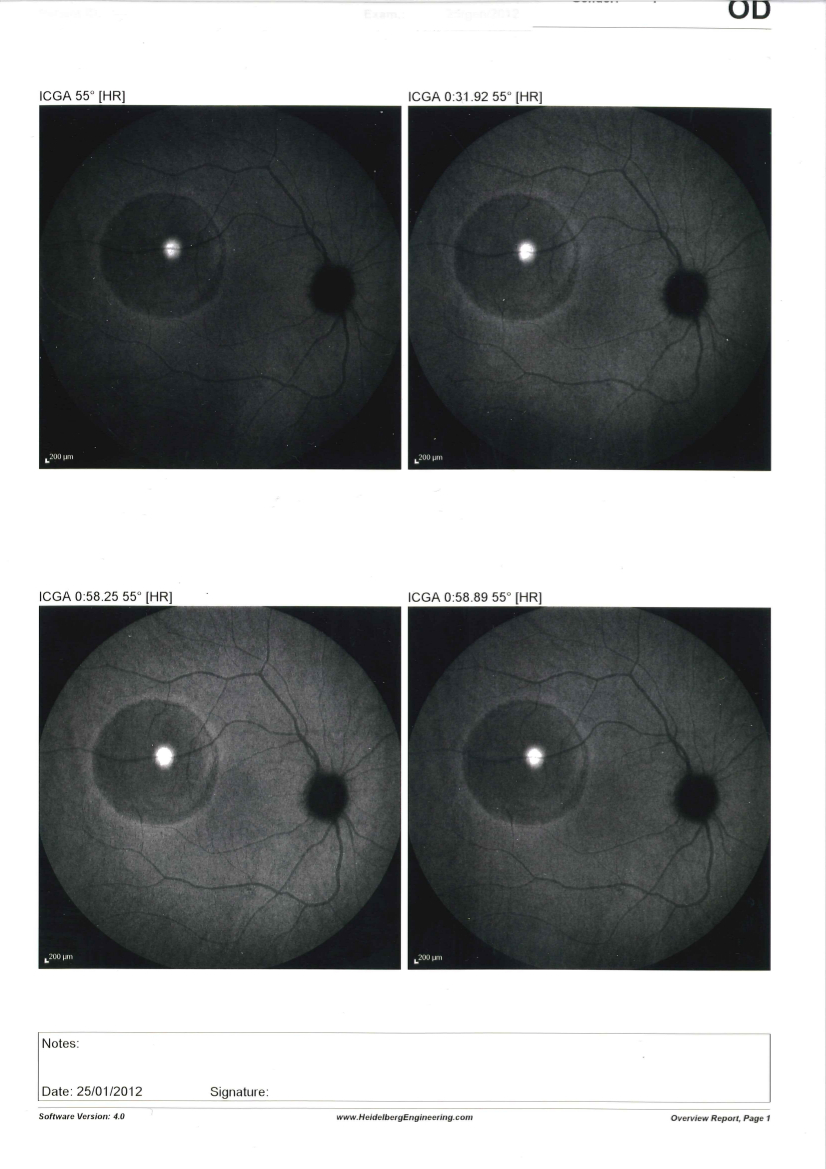

7 Membrana neovascolare sottoretinica (maculopatia) maculare in miope

Paziente di 46 anni riferisce calo visivo nell'occhio di sinistra da circa 2 settimane, l'obiettività oculistica è la seguente:

vod: 10/10 con correzione ottica

vos: 8-9/10 con correzione ottica

too: 15 mmhg

boo: nella norma

fod: sospetto distacco sieroso maculare

fos: nei limiti di norma

Effettuato OCT (vedi allegato): nell'occhio sinistro si evidenzia un distacco sieroso maculare

Effettuata fluorangiografia (vedi allegato): nell'occhio sinistro si evidenzia una membrana neovascolare sottoretinica maculare

Effettuata terapia con iniezioni intravitreali di farmaci anti-VEGF, la neovascolarizzazione è totalmente regredita e la paziente vede con l'occhio sinistro 10/10 con correzione ottica.

Questo caso poteva essere di difficile interpretazione all'inizio per l'assenza di emorragie retiniche maculari che indicassero la presenza di una neovascolarizzazione e per l'evidenza all'OCT di un distacco sieroso che poteva essere anche di altra natura, la fluorangiografia ha permesso di evidenziare l'esatta causa.

Questo ci dimostra come OCT e fluorangiografia siano esami entrambi importanti e con informazioni complementari e spesso è necessario effettuarli entrambi per un corretto studio delle maculopatie.